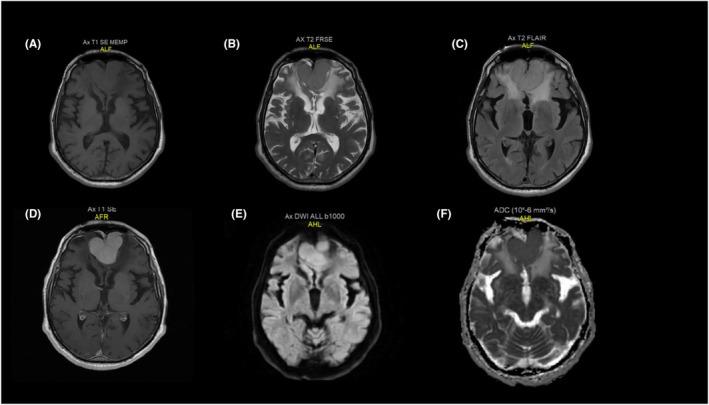

An 83-year-old male with a history of tension-type headaches was evaluated. He was conscious with no focal neurological deficits. His brain MRI revealed an enhancable bifrontal tumor originating from falx cerebri and superior sagittal sinus dura. Due to the patient's preference and decline for gross total resection, she underwent a stereotactic biopsy. The pathology was positive for Rosai-Dorfman diseases. He received definitive targeted radiation with a total dose of 4500 cGy administered in 200 cGy daily fractions. His 4-year follow-up showed regional tumor control with excellent neurological outcome.

对一名有紧张型头痛病史的83岁男性进行了评估。他意识清醒,无局灶性神经功能缺损。他的脑部MRI显示一个可强化的双额叶肿瘤,起源于大脑镰和上矢状窦硬脑膜。由于患者偏好并拒绝全切除,她接受了立体定向活检。病理结果显示罗萨伊-多夫曼病阳性。他接受了总剂量为4500 cGy的确定性靶向放疗,每日分次给予200 cGy。他的4年随访显示局部肿瘤得到控制,神经功能结果良好。